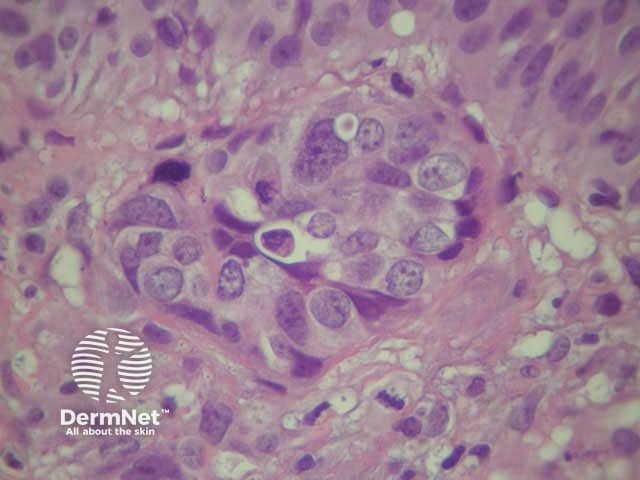

A skin biopsy of the nodule should be performed.

Histologically most tumours are adenocarcinoma and the likely origin may be suggested by histochemical stains on the biopsy and tumour markers such as CEA.